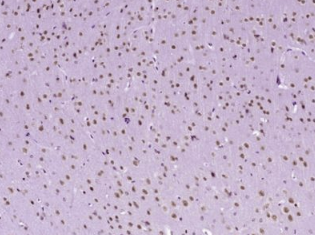

多聚甲醛固定,石蜡包埋(小鼠脑);用柠檬酸钠缓冲液(pH6.0)煮沸15min后获得抗原;用3%过氧化氢阻断内源性过氧化物酶20分钟;阻断缓冲液(正常山羊血清)在37℃下30min;用(磷酸-ATF2(Ser90))多克隆抗体进行抗体孵育。1:400在4°C下过夜,然后根据SP试剂盒(兔子)说明和DAB染色进行操作。